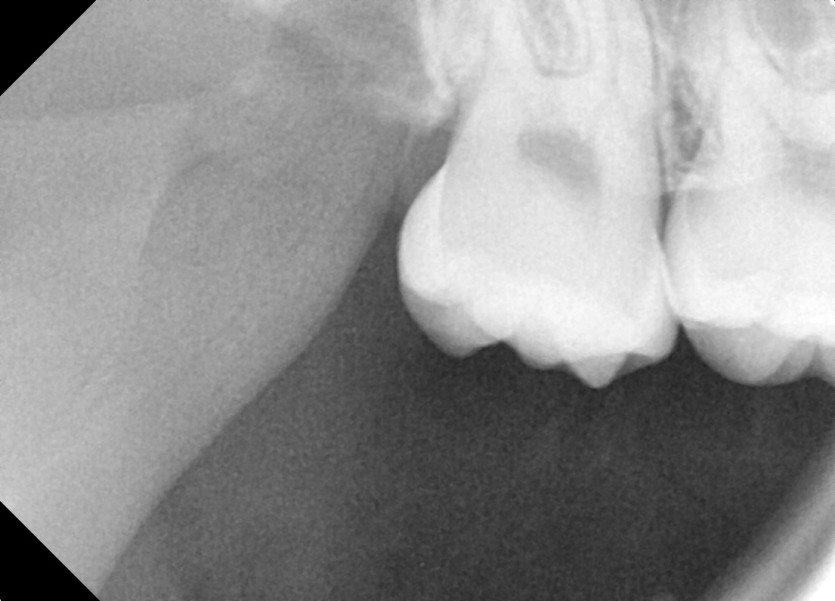

#18,48 사랑니 발치

구강 외과 전문의가 당일 발치했습니다.